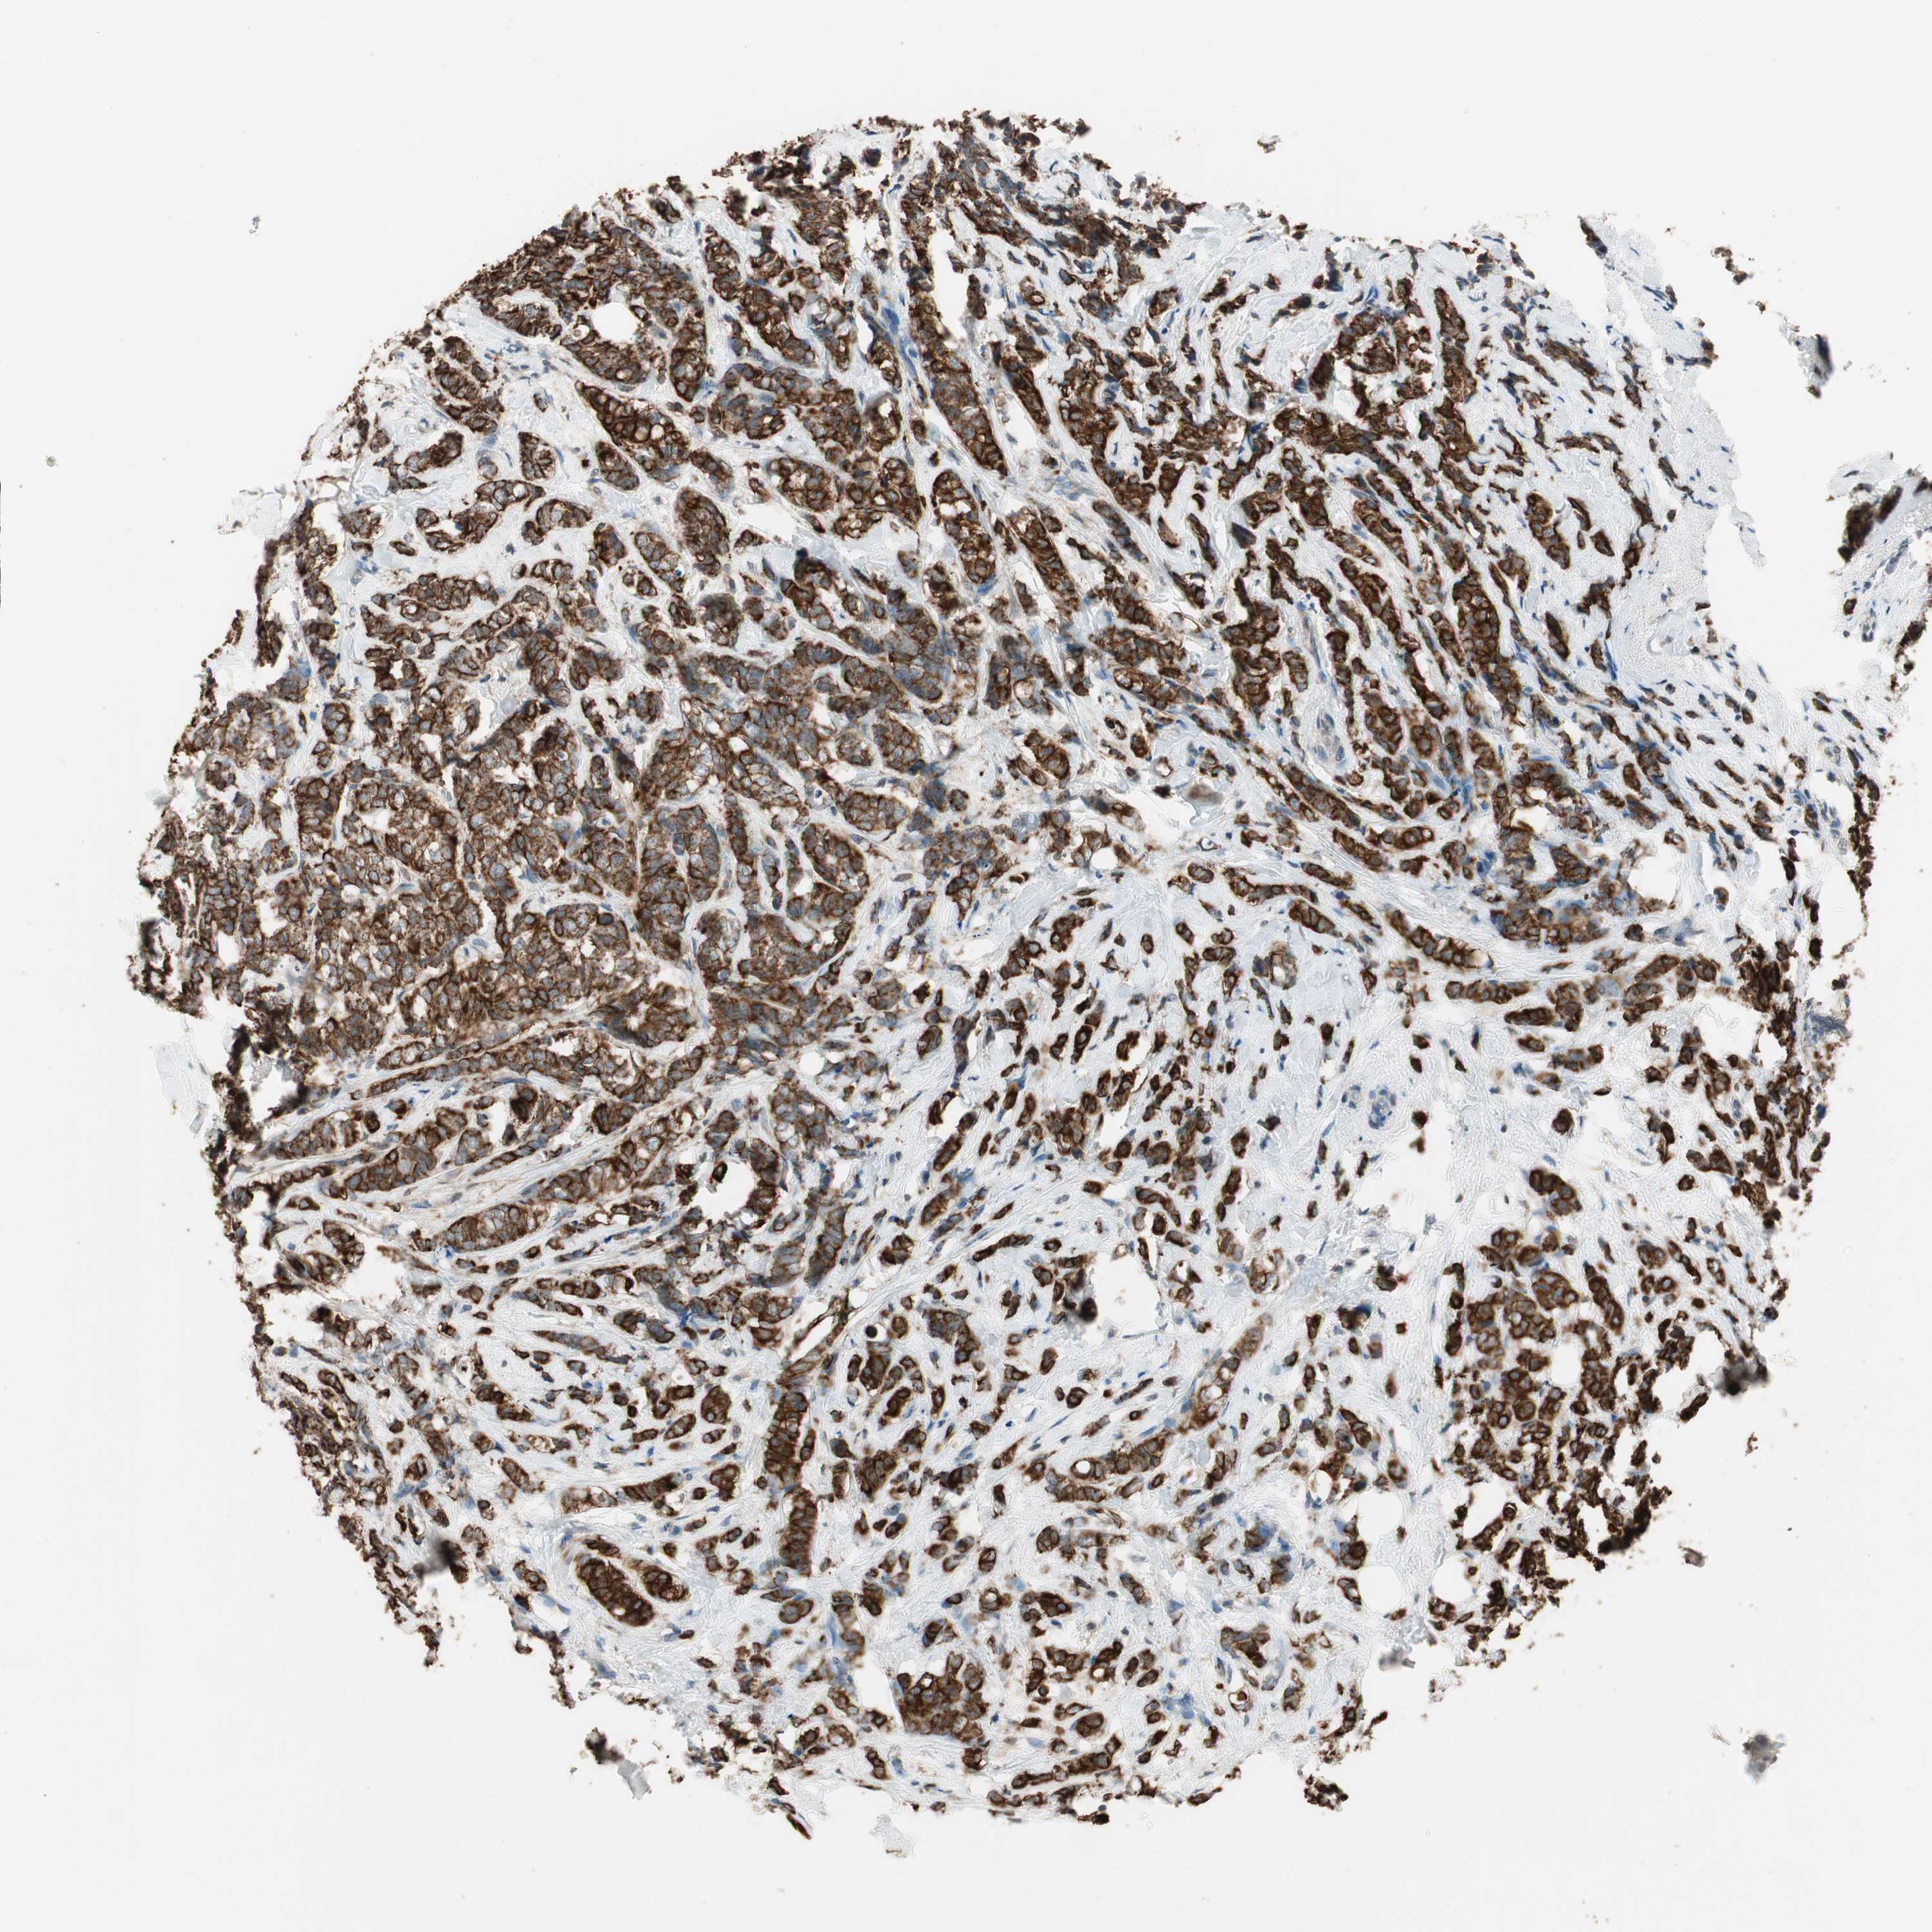

CANCER BREAST CANCER Show tissue menu

BRCA TCGA BRCA VALIDATION PROTEIN EXPRESSION